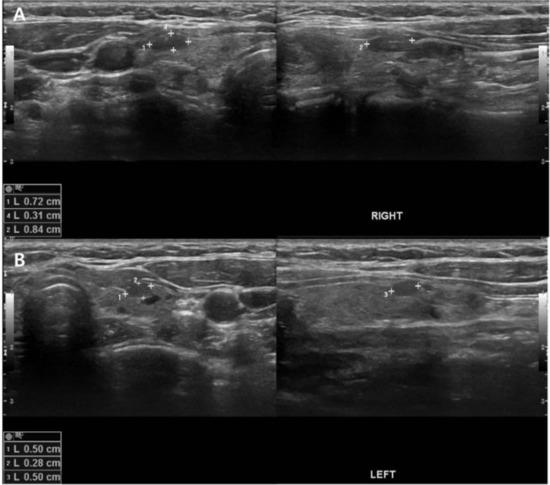

Role of 11C-Methionine PET/CT in 99mTc-Sestamibi-Negative Parathyroid Adenoma: A Case Report

- Braeuning, U.; Pfannenberg, C.; Gallwitz, B.; Teichmann, R.; Mueller, M.; Dittmann, H.; Reimold, M.; Bares, R. 11C-methionine PET/CT after inconclusive 99mTc-MIBI-SPECT/CT for localisation of parathyroid adenomas in primary hyperparathyroidism. Nuklearmedizin 2015, 54, 26–30. [Google Scholar] [CrossRef] [PubMed]

- Noltes, M.E.; Coester, A.M.; van der Horst-Schrivers, A.N.; Dorgelo, B.; Jansen, L.; Noordzij, W.; Lemstra, C.; Brouwers, A.H.; Kruijff, S. Localization of parathyroid adenomas using 11C-methionine PET after prior inconclusive imaging. Langenbecks Arch. Surg. 2017, 402, 1109–1117. [Google Scholar] [CrossRef] [PubMed]

- Lenschow, C.; Gassmann, P.; Wenning, C.; Senninger, N.; Colombo-Benkmann, M. Preoperative 11C-Methionine PET/CT enables focused parathyroidectomy in MIBI-SPECT negative parathyroid adenoma. World J. Surg. 2015, 37, 1750–1757. [Google Scholar] [CrossRef] [PubMed]

- Traub-Weidinger, T.; Mayerhoefer, M.E.; Koperek, O.; Mitterhauser, M.; Duan, H.; Karanikas, G.; Niederle, B.; Hoffmann, M. 11C-methionine PET/CT imaging of 99mTc-MIBI-SPECT/CT-negative patients with primary hyperparathyroidism and previous neck surgery. J. Clin. Endocrinol. Metab. 2014, 99, 4199–4205. [Google Scholar] [CrossRef] [PubMed][Green Version]

- Yuan, L.; Liu, J.; Kan, Y.; Yang, J.; Wang, X. The diagnostic value of 11C-methionine PET in hyperparathyroidism with negative 99mTc-MIBI SPECT: A meta-analysis. Acta Radiol. 2017, 58, 558–564. [Google Scholar] [PubMed]